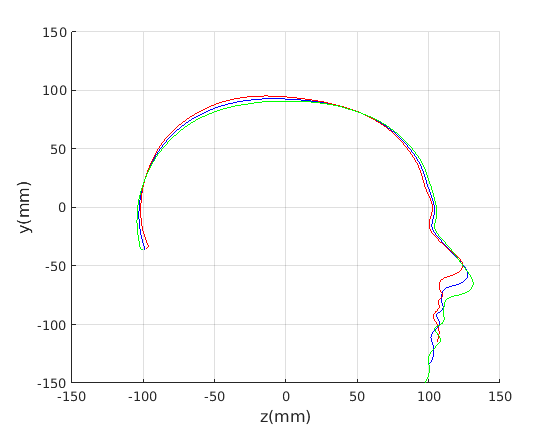

6.2 Model compactness

We evaluate both model construction with geometric alignment (ECN normalisation) and model construction with alignment by Generalised Procrustes Analysis (GPA). Model compactness is a key performance criterion for the correspondence and alignment processes that generate that model [31]. A more compact model has a smaller variance and requires fewer parameters to express a particular shape instance than less compact model. Cumulative variance plots generated by application of PCA are a useful measure of compactness, with more rapidly rising curves indicating more compact models. In Fig. 23 and Fig. 24 we present the cumulative variance plots for our profile models using automatic and manual landmarking respectively and aligned with either ECN or GPA alignment schemes.

Comparing the compactness of the models produced by automatic and manual facial profile landmarking, we found that the performance is almost identical and there is no statistical significance in performance given the modest test size of 100 faces. For example, for the full head profile, with no scale normalisation, the automatic landmarks give cumulative variances of 51.5%, 76.5%, 88.9% and 91.3% over the first four modes whereas the manual landmarks give 50.8%, 76.5%, 88.9% and 91.2%.

A point to note is that whatever model is built, ECN always produces more compact models than GPA. The difference is more marked when a head model is built (cranium and face) compared to cranium only. This can be explained by the fact that the cranium has 210 points sampled on its surface, whereas the face has 128. ECN focusses on aligning the majority group (cranial points) and does not allow more extreme features (such as a large nose) to influence this. GPA on the other hand does, so relatively few points around the nose region can influence alignment over the whole cranium. ECN normalisation is more appropriate when we are interested in cranial shape.